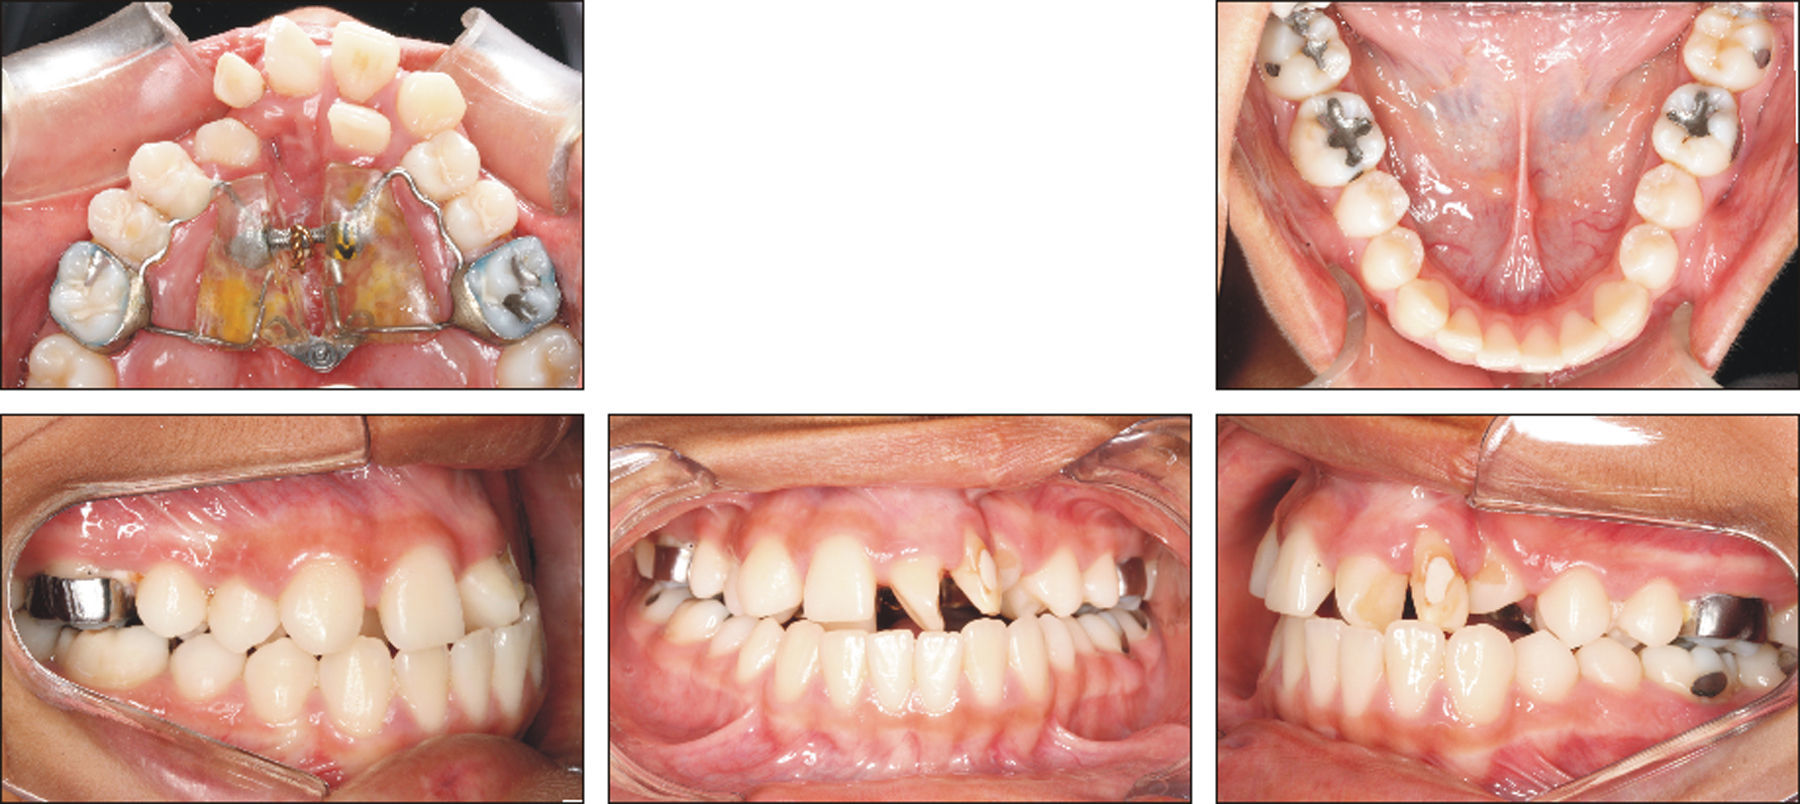

A paciente A, do sexo feminino, passou por procedimentos cirúrgicos condizentes ao protocolo de reconstrução da fenda labiopalatina na primeira infância, como queiloplastia, palatoplastia e faringoplastia12. Como esperado, houve redução da largura do arco dentário superior devido à junção dos segmentos e uma limitação no crescimento do terço médio da face. Aos 12 anos, em estágio pré‐puberal, CS1 de maturação óssea13, a paciente apresentava clinicamente um perfil côncavo, molares com padrão de oclusão em Classe I de Angle, atresia transversal maxilar severa na região anterior e mordida cruzada anterior (figs. 1 e 2). Pelo exame da telerradiografia em norma lateral da face, observou‐se a sugestão de estreitamento e constrição das vias aéreas, relação esquelética de Classe I (ANB=3,6°), mas apresentando uma tendência à Classe III (Wits=−3,3mm), maxila retroposicionada em relação à base do crânio (SNA=80,6°), bom posicionamento de incisivos superiores (1.NA=3,5mm; 1.NA=21,9°) e projeção vestibular de incisivos inferiores (1.NB=8,9mm; 1.NB=28,1°; IMPA=93,7°) (fig. 3). Como parte da documentação ortodôntica inicial para o planeamento do tratamento, que incluía os enxertos ósseos na região da fenda, a paciente foi submetido a uma tomografia computadorizada por feixes cônicos (TCFC), no tomógrafo i‐CAT (Imaging Sciences International, Hatfield, Pennsylvania, Estados Unidos da América [EUA)), com field of view (FOV) de crânio estendido (23cmx17cm), voxel de 0,3mm3, 36,90mA, 120kV e tempo de exposição de 40 segundos. Frente a todas as características encontradas, foi determinada uma maior necessidade de ERM na região anterior, em preparação para enxerto ósseo e tratamento ortodôntico corretivo. Após o diagnóstico, foi escolhido o expansor em leque. O aparelho foi confeccionado com um parafuso expansor em leque (Morelli, Sorocaba, São Paulo, Brasil). O aparelho possui bandas nos primeiros molares permanentes e uma dobradiça na região posterior, fixada em acrílico, de onde partem extensões de fio 0,9mm, apoiadas nas superfícies palatinas dos molares decíduos ou pré‐molares. Este aparelho é considerado dentomucossuportado (fig. 4).

O histórico de cirurgias do paciente B, sexo masculino, se assemelha ao da paciente anteriormente descrito, assim como os efeitos sobre sua maxila e suas características relativas ao perfil facial, padrão esquelético e dentário (figs. 5 e 6). Igualmente acompanhado pelo CENTRARE, concordou‐se em iniciar a ERM aos 12 anos. Realizados exames clínicos e TCFC, observou‐se: tendência a uma má oclusão esquelética de Classe III (ANB=0,6°; Wits=–2,1mm), maxila bem posicionada em relação à base do crânio (SNA=81,1°), incisivos superiores retroposicionados e retroinclinados (1.NA=‐1,5mm; 1.NA=11,6°) e incisivos inferiores bem posicionados na base óssea (1.NB=28,5 graus; IMPA=92,8 graus) (fig. 7). Diante da necessidade de expansão limitada à região anterior, foi instalado em JFRL o disjuntor mini‐Hyrax invertido com BTP11. Confeccionado com um mini parafuso (Variety Expander, DynaFlex, Saint Ann, Missouri, EUA) posicionado na região mais anterior possível do palato. Extensões provenientes do parafuso (fio 1,4mm) contornaram a superfície palatina dos caninos, passando pelas bandas nos primeiros pré‐molares e chegando até à superfície palatina dos segundos pré‐molares. Além disso, uma BTP (fio 0,9mm) foi soldada em bandas nos primeiros molares permanentes (fig. 8).

Fotografias intraorais, após a expansão com o aparelho mini‐Hyrax invertido com BTP. Mini parafuso posicionado na região anterior do palato, bandas nos primeiros pré‐molares, extensões apoiadas nos caninos até aos segundos pré‐molares, BTP (fio 0,9mm) soldada em bandas nos primeiros molares permanentes e contenção (fio de latão 0,7mm).

O expansor da paciente A foi cimentado com Ultra Band‐Lok Blue (Reliance Orthodontics Products, Itasca, Illinois, EUA). O expansor do paciente B foi cimentado com Vidrion C (SS White, Rio de Janeiro, Brasil). As bandas receberam tratamento prévio com óxido de alumínio (partículas de 50 micrômetros), para aumento da retenção. No expansor em leque foi utilizada resina composta (Z 100tm Restorative, 3M ESPE, Dental Products, Saint Paul, Minnesota, EUA) como apoio na região de pré‐molares durante a expansão. O protocolo de ativação foi de meia volta no parafuso por dia (¼ de volta pela manhã e ¼ de volta à noite). A ativação foi realizada até que fosse obtida a sobrecorreção da atresia maxilar, representada pela cúspide palatina do primeiro pré‐molar superior ocluindo com a ponta da cúspide vestibular do primeiro pré‐molar inferior (figs. 4 e 8). Após a fase de ativação, os disjuntores foram travados com fio de latão 0,7mm, para fase de contenção. Depois de 3 meses estável, os expansores foram substituídos por uma BTP com extensões anteriores de fio 0,9mm, até que a próxima etapa do tratamento ortodôntico fosse iniciada. No rápido intervalo, cerca de 24 horas, entre a retirada dos expansores e a instalação da BTP, foi realizada uma segunda TCFC nos mesmos padrões das anteriores, com o objetivo de planejar o enxerto ósseo.